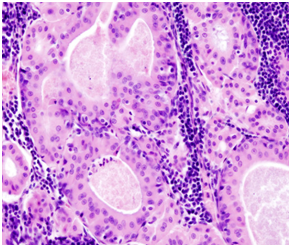

An 80-year-old Caucasian woman presented in our ENT department due to a progressive swelling on the left parotid gland during a period of two months. The physical examination showed a soft and mobile mass on the left parotid gland. The flexible fiber optic laryngoscopy showed a mass in the left laryngeal ventricle with intact laryngeal mucosa. The ultrasound of the salivary glands showed a multi - lobular tumor of both left and right parotid glands. The MRI scan showed a 1.2 x 1.1cm solid tumor in the left supraglottic region, without infiltration of adjacent tissues. In the parotid region was a 2.7 x 1.8cm solid mass in the left parotid gland as well as a 0.8 x 1.2cm solid mass in the inferior lobe of the left parotid gland (Figure 1&2). The patient was operated under general anesthesia. The larynx tumor was resected via transoral laser excision and the parotid tumor of the left side was resected via lateral parotidectomy. The histopathological examination showed a cystadenolymphoma that consist of an oncocytic epithelial cell component arranged in double layers, which develops cysts and papillary projections, and a variable amount of lymphoid tissue with germinal centers (Figure 3). An oversupply of lymphoid stroma with a characteristic formation of lymph follicles (Figure 4) was observed in all histological specimens with hematoxylin and eosin stain. There were no granulomas and no evidence of bacterial, fungal, or parasitic infection. The final diagnosis was a cystadenolymphoma in the morgagni sinus as well as multiple lesions in the parotid gland, compatible with a cystadenolymphoma. After consulting the patient, an ultrasound controlled fine needle aspiration of the tumor of the right parotid gland was performed. The histopathological examination showed a cystadenolymphoma of the right parotid gland.